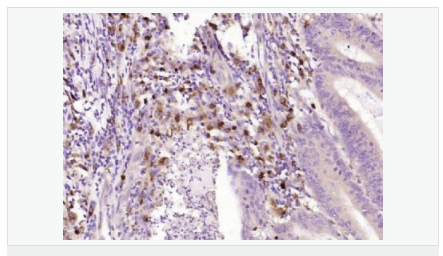

| 產(chǎn)品應(yīng)用 | WB=1:500-2000 ELISA=1:5000-10000 IHC-P=1:100-500 IHC-F=1:100-500 ICC=1:100-500 IF=1:100-500 (石蠟切片需做抗原修復(fù)) not yet tested in other applications. optimal dilutions/concentrations should be determined by the end user. |

| 細(xì)胞定位 | 細(xì)胞漿 |